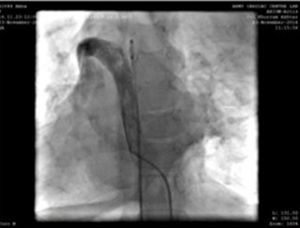

Right femoral vein and artery were cannulated used 5F radial sheath. During the procedure, we found the inferior vena cava (IVC) to drain across the azygous continuation into the right superior vena cava and then track through the dilated coronary sinus in the right atrium. A decision to carry out the procedure from the left internal jugular vein (accessed with 5F radial sheath) was made.

Puncture of the left jugular vein, and 5F angiography catheter, showing the upper arm vein - superior vena cava - right atrium connection path.